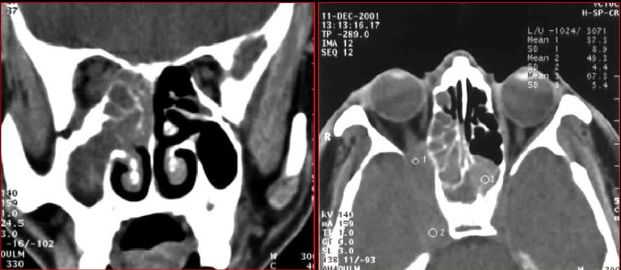

慢性多发鼻窦炎—MRI